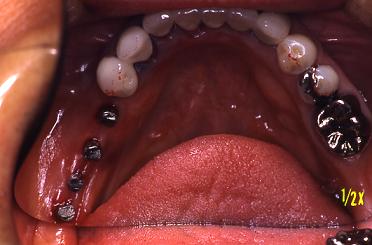

冠が入りました